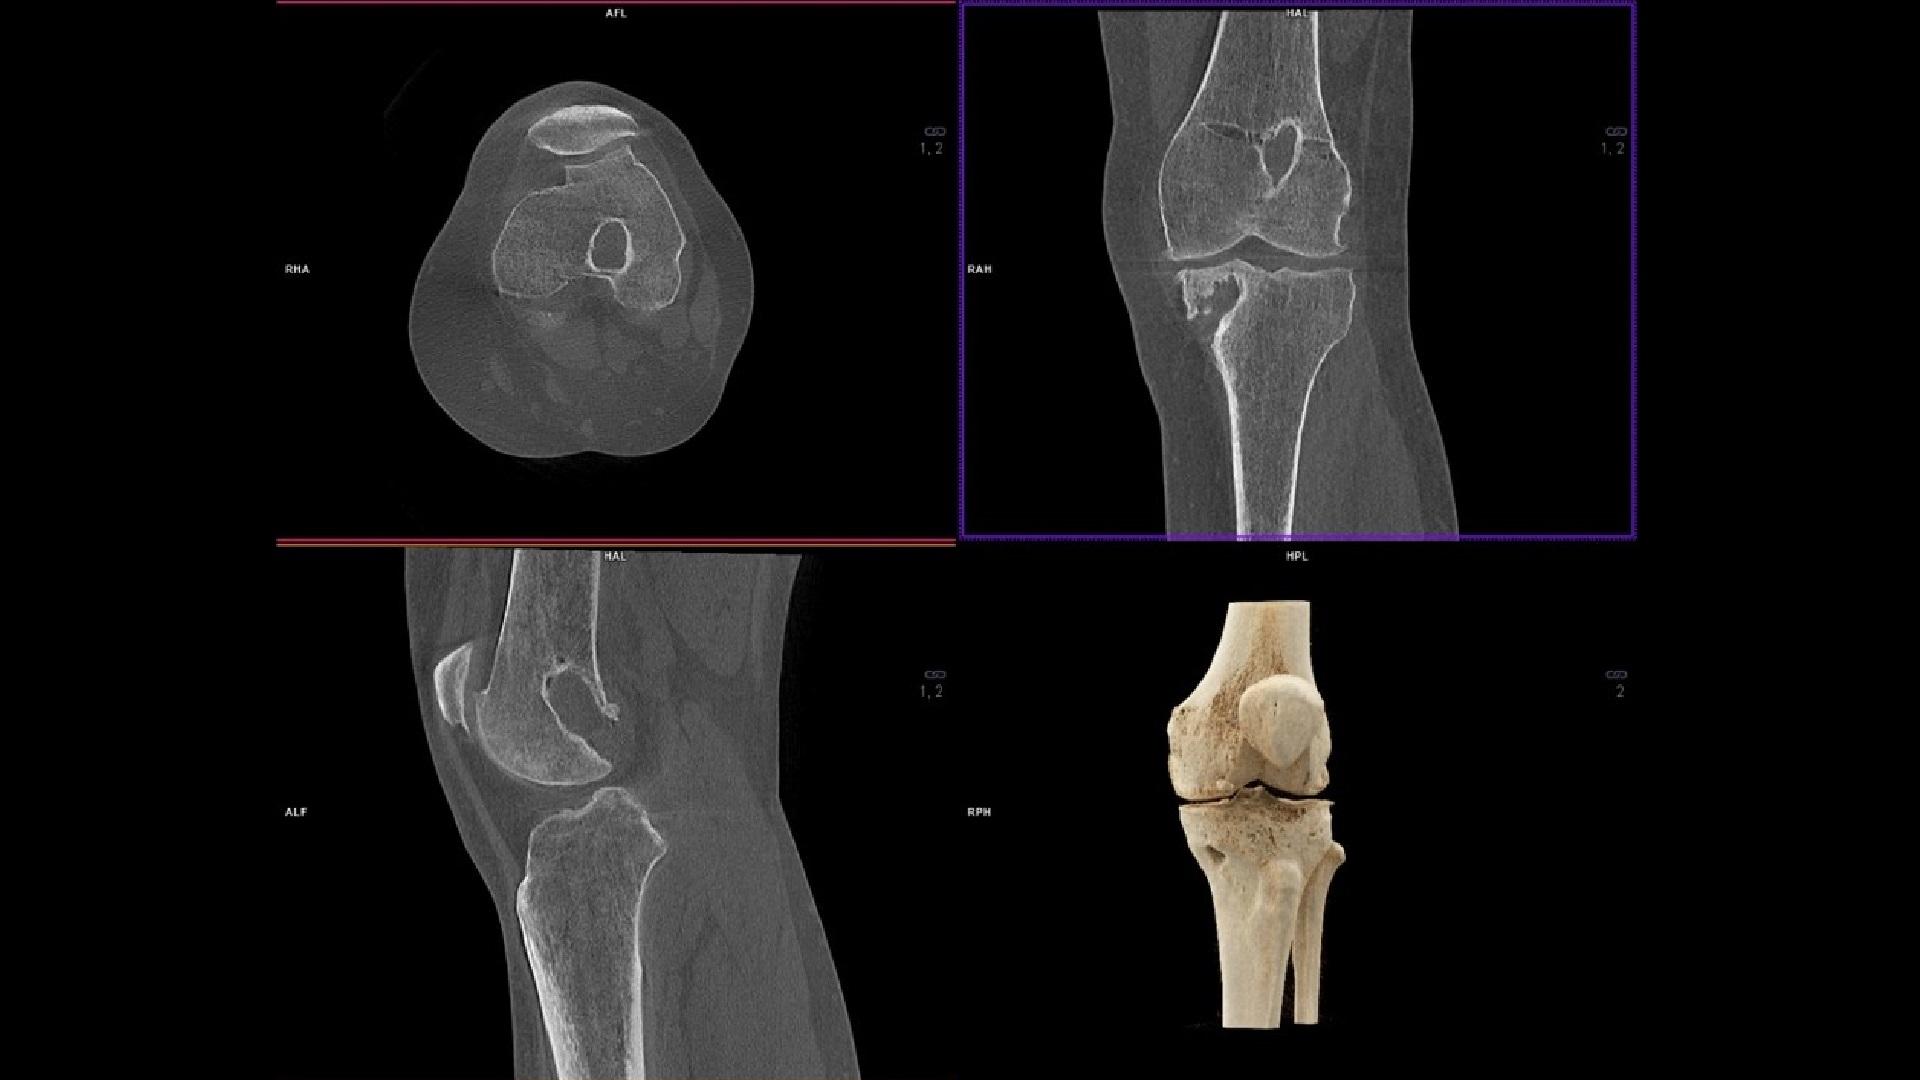

Acquire diagnostically relevant 3D bone imaging with optimized Real 3D2 for improved image quality, more stable patient positioning, fewer artifacts and streamlined, faster exams. The new Real 3D Hi-Res2 functionality is designed to get even higher spatial resolution for images of the hand, wrist and elbow.